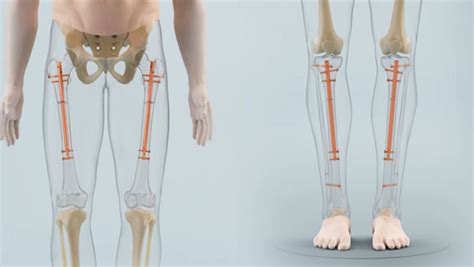

At its core, leg lengthening surgery, medically known as distraction osteogenesis, relies on the body’s innate ability to regenerate new bone and soft tissue. The process begins with an orthopedic surgeon making a precise cut in the bone, known as an osteotomy. Once the bone is divided, a specialized device, usually an internal intramedullary nail, is implanted into the marrow cavity.

After the initial surgery, a period called the "distraction phase" begins. During this time, the device is gradually lengthened—often via an external remote control—by a small amount each day, typically about one millimeter. This slow separation creates a gap where new bone tissue, nerves, and blood vessels slowly form to bridge the space. Following the distraction phase, the bone must undergo a consolidation phase, where the newly formed bone mineralizes and hardens to reach full strength.